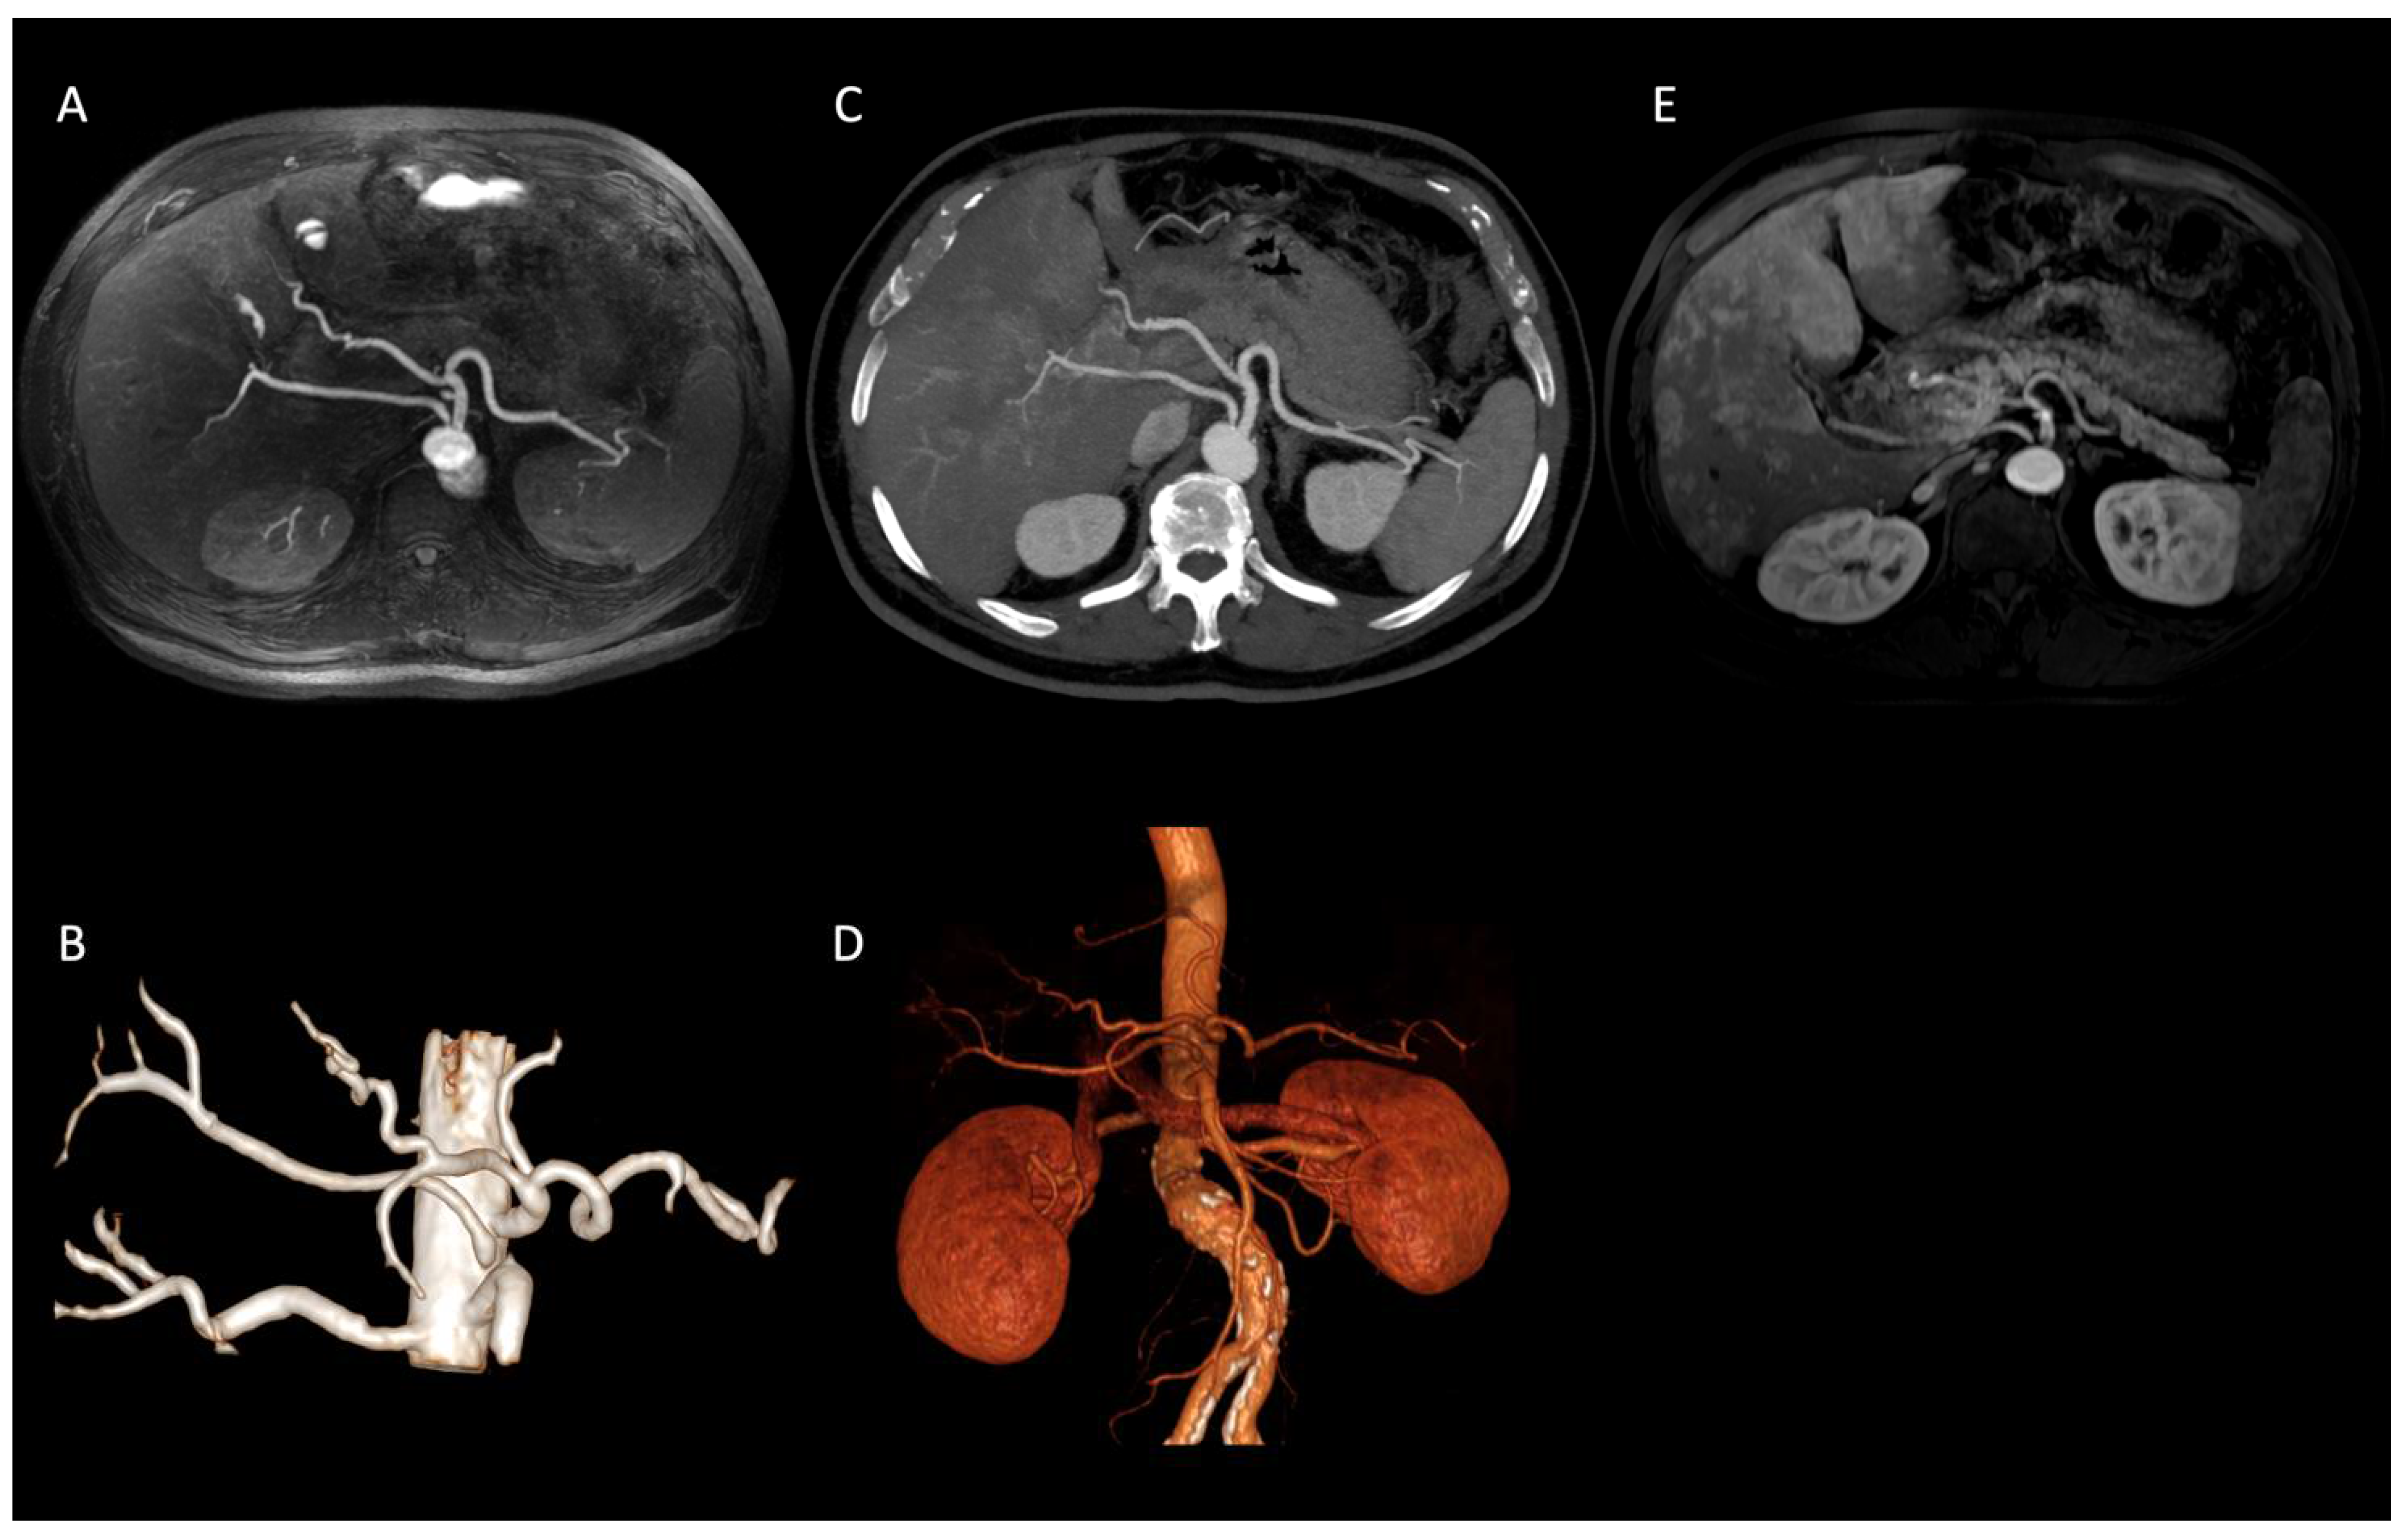

In our population, we observed several visceral vessels variants. Type I turned out to be the most common pattern, being present in 47 patients (67%), according to the incidence reported in literature (55% to 81%) [12,22]. The other variants were distributed as follows: Type V in 10 patients (14%); Type VI in 6 patients (9%); Type III in 2 patients (3%); Type IX in 2 patients (3%); Type XI in 2 patients (3%) (Figure 2); Type VII in 1 patient (1%).

Figure 2. Axial IFIR-MRA (A) and CTA (B) MIP reconstructions properly showing the direct origin of the right hepatic artery from the aorta (Type XI according to Michels’ classification system) and the remaining main celiac trunk branches up to the proximal bifurcations (spleen and hepatic hilum). On MRA (C) MIP reconstruction image quality and resolution are lower, not allowing the proper assessment of proximal bifurcations. IFIR-MRA (D) and CTA (E) 3D reconstructions, showing a comparable diagnostic performance.